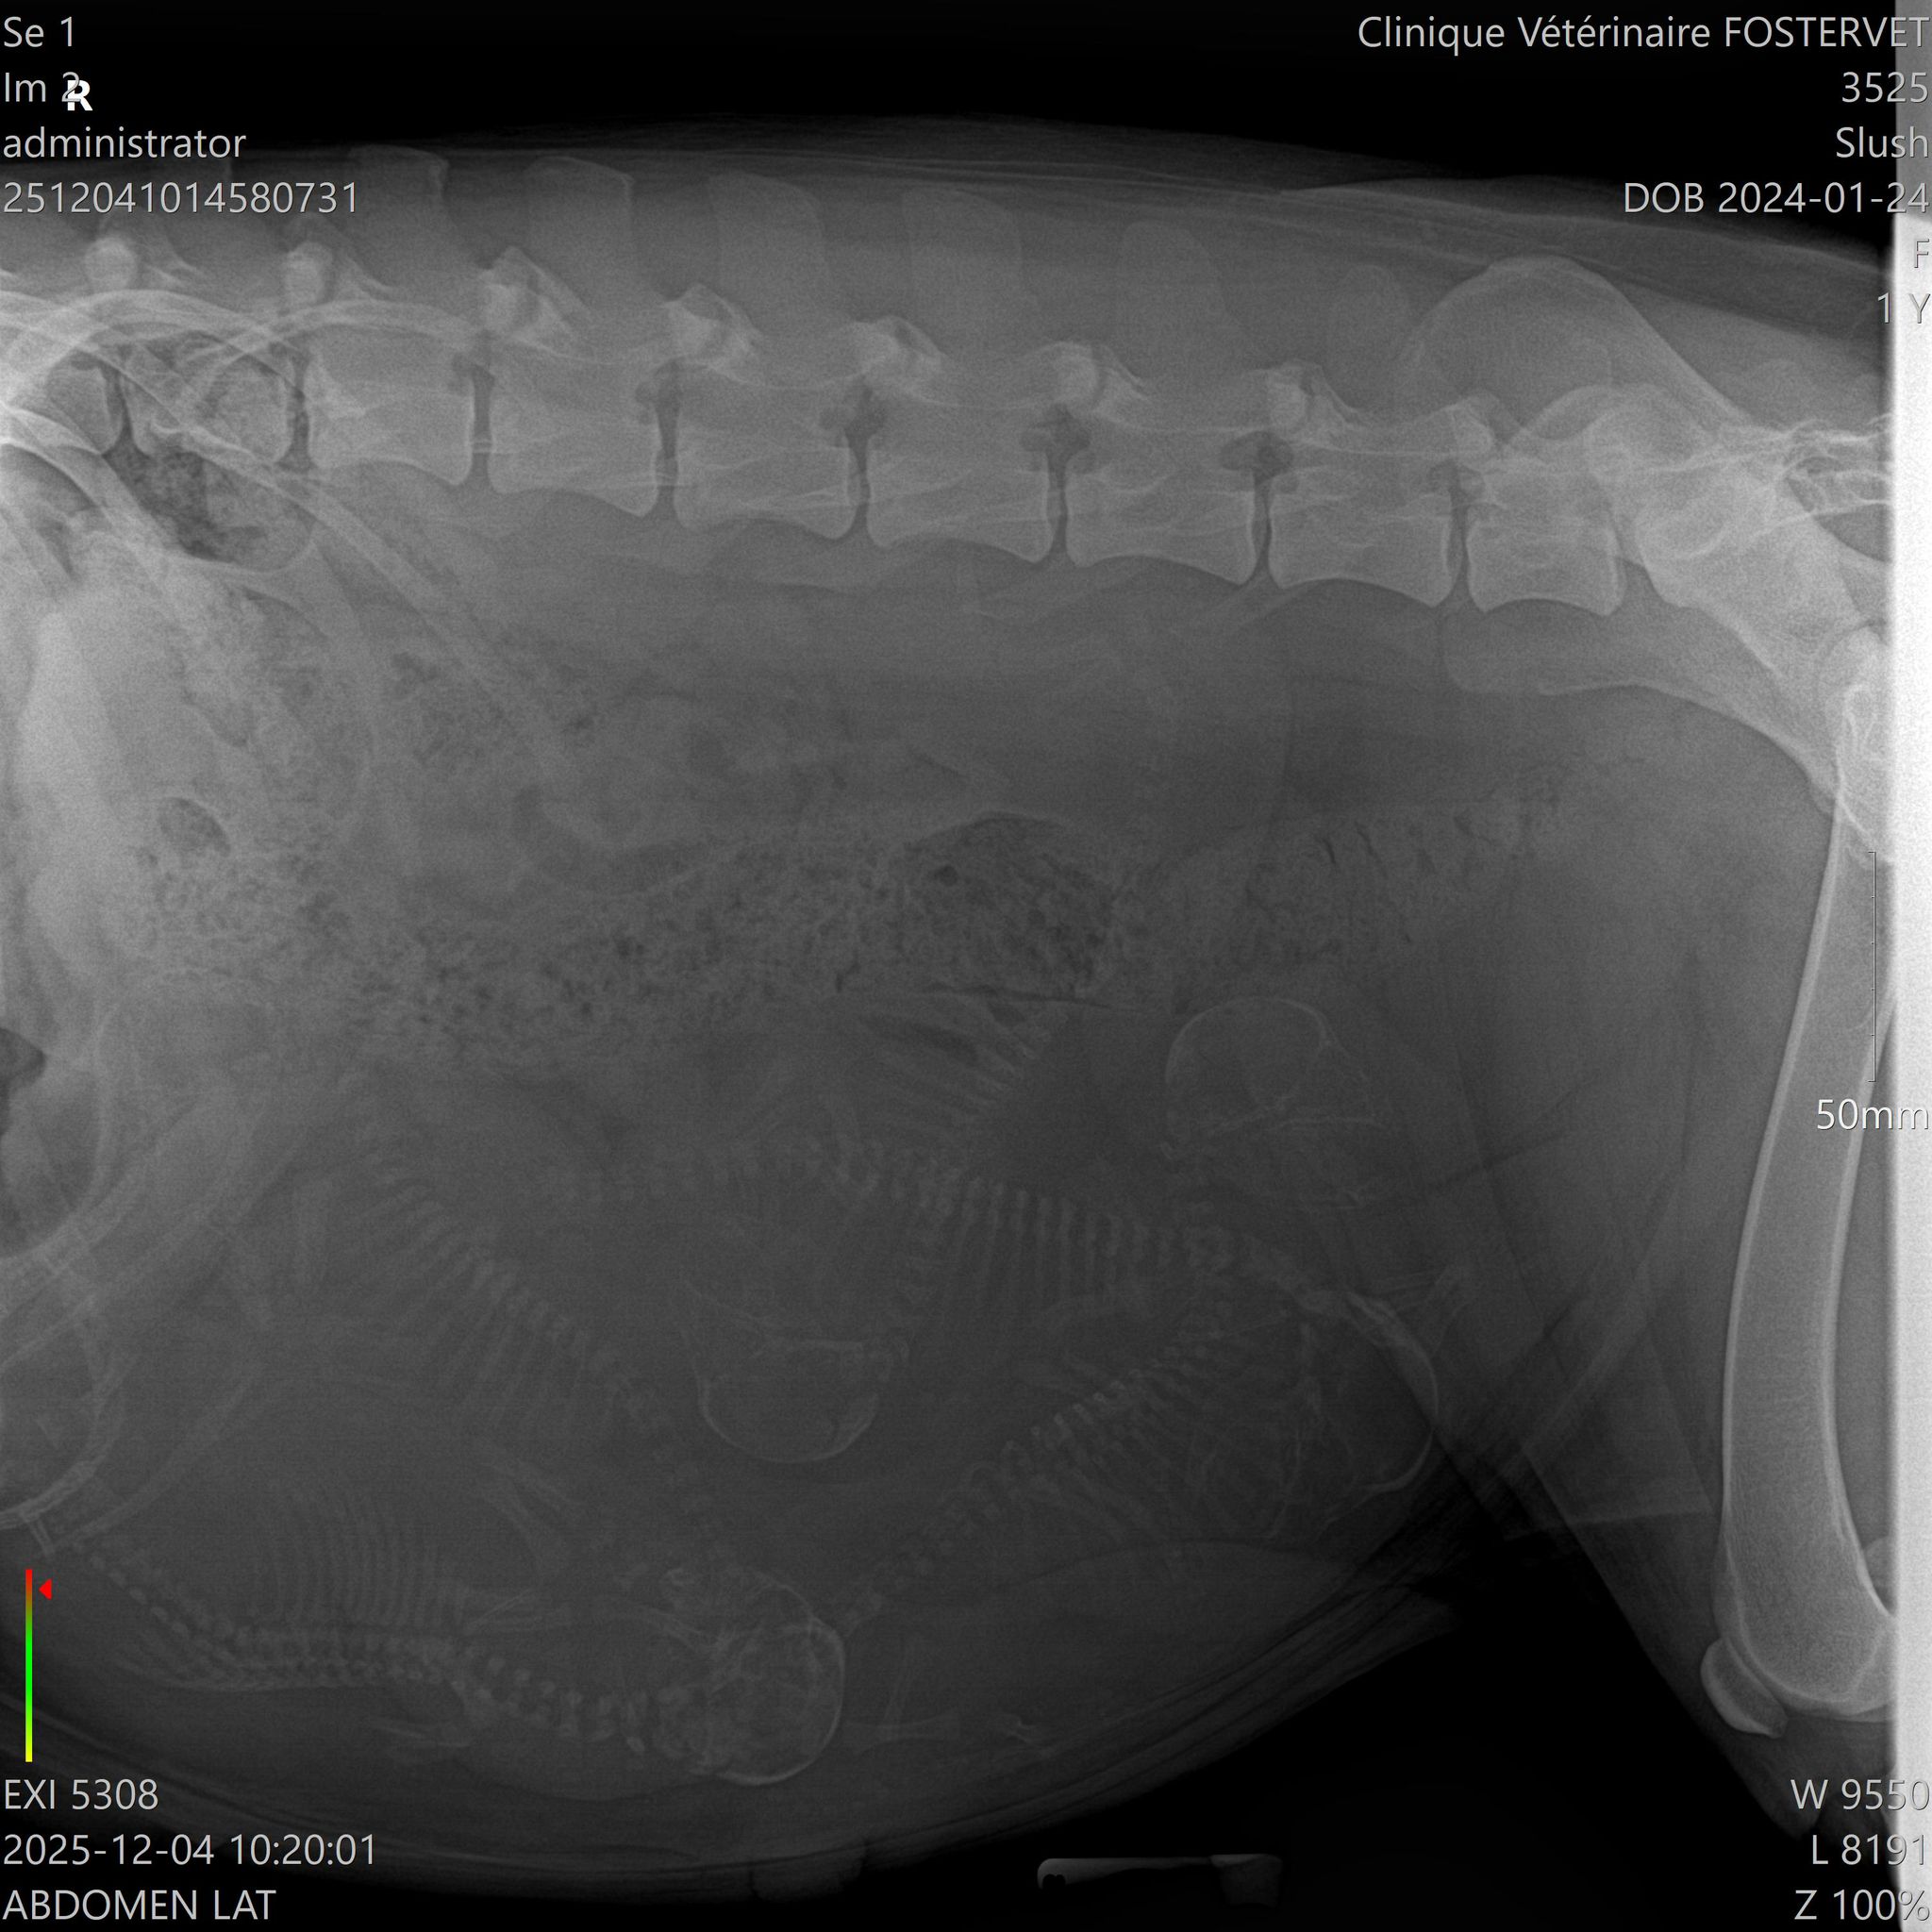

Slush x Conor

Litter born December 10, 2025

4 males and 1 female ( all black ) : Lennon, McCartney, Harrison, Ringo and Yoko